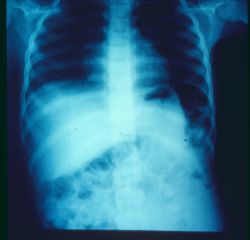

سل شکمی Abdominal T B